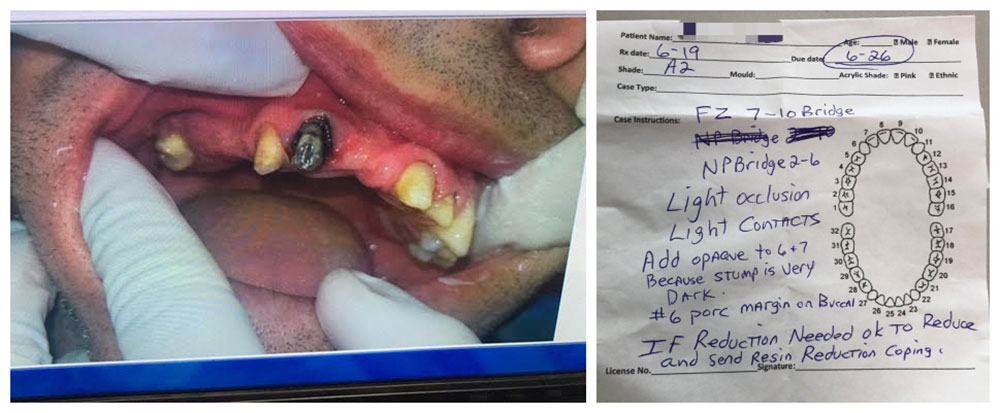

Soon we got the package in our Hong Kong office. After unpacking the case, we found there were quite a few stone models (must have been from other labs). Thankfully, the customer also sent new impressions, and a photo showing the patient’s teeth.

It is important that we have new impressions, new bites and photos, if it is for a remake case, especially a case from another dental lab. For example, in this photo, we learn the stump shade of one tooth is very dark and need special treatment.